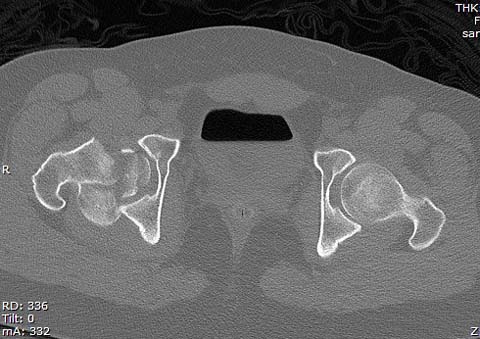

Здесь клинические примеры: Первый случай передний доступ, второй с ICP

monitor Flipp Trochanteris

и с переломом заднего края.